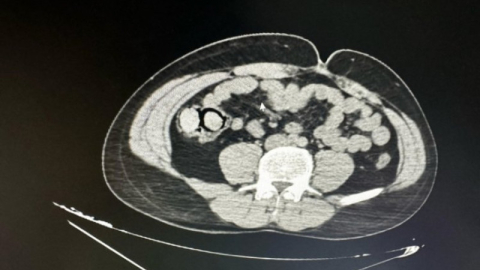

Bingöl'de akıllara durgunluk veren bir olay gerçekleşti. Otobüs yolculuğu sırasında polis ekiplerince durdurulan yabancı uyruklu iki şahsın midesinden 10 parça halinde 113 gram metamfetamin çıktı.

Bingöl Emniyet Müdürlüğü Narkotik Suçlarla Mücadele Şube Müdürlüğüne bağlı narko-timleri akıllara durgunluk veren bir uyuşturucu kaçakçılığını çözdü. Ekiplerin çalışmaları neticesinde otobüs ile Bingöl'e gelen şüpheli yabancı uyruklu 2 şahsın iç beden muayenesinde 10 parça halinde 113 gram metamfetamin maddesi tespit edildi. Emniyetteki işlemlerinin ardından mahkemeye çıkarılan 2 şahıs, uyuşturucu madde ticareti yapmak suçundan tutuklanarak Elazığ Kapalı ceza infaz kurumuna teslim edildi.